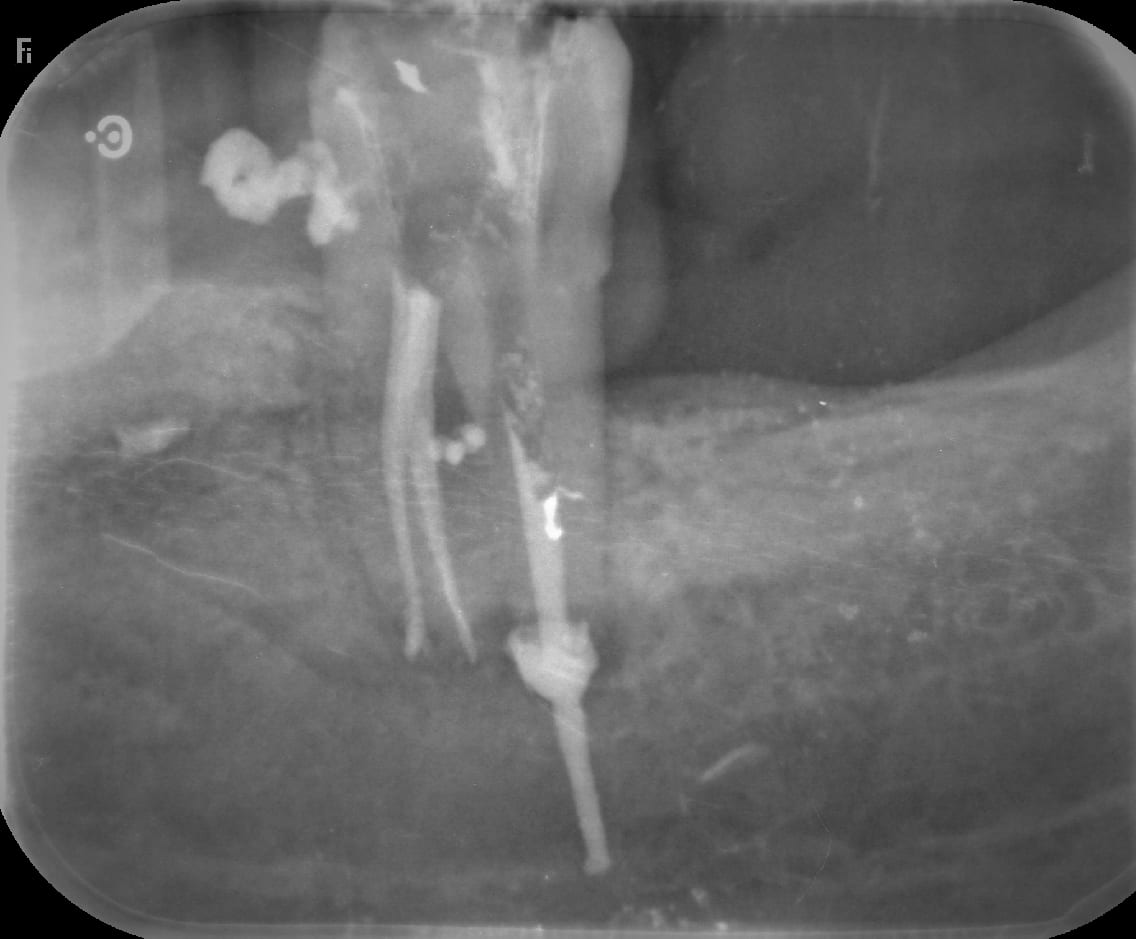

que pcq c est un diabétique , j allais le prendre en urgence pour un abcès et que j allais lui faire le coup du S files avec de l' obturation tridimensionnelle ?

là on est plutot dans X files , la 5 eme dimension .

bon forcement , dans l etat ça va moins bien marcher , non ?

Je suppose que c est un kyste , une image radio , du pus qui sort , un apex sucé, machination sans anesthésie...bon après faut voir mais ça peut être quoi d autre ? .

Avec une radio comme ça je ne conclue rien du tout, pas plus avec ton « pus qui sort ».

C est sur que je l ai bien machiné au spadden , mais non , j ai vérifié l outil , je ne l ai pas cassé dedans .